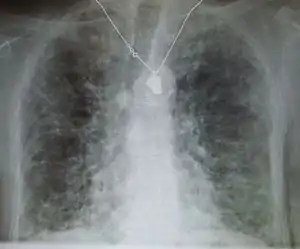

Side effects of amiodarone include various pulmonary effects.[22] The most serious reaction that is due to amiodarone is interstitial lung disease. Risk factors include high cumulative dose, more than 400 milligrams per day, duration over two months, increased age, and preexisting pulmonary disease. Some individuals were noted to develop pulmonary fibrosis after a week of treatment, while others did not develop it after years of continuous use. Common practice is to avoid the agent if possible in individuals with decreased lung function.